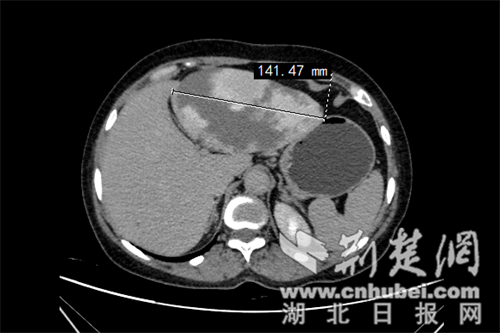

術(shù)前腹部CT照片:

近日,今年50多歲的任女士突感腹脹。起初,她并未將腹脹放在心上,以為只是普通的腸胃不適。但隨著時間的推移,任女士少量進(jìn)食就會導(dǎo)致嚴(yán)重腹脹,而且在肚子上還能摸到隆起的包塊,遂趕緊到十堰人醫(yī)肝膽胰腺外科門診就診。然而,初步的檢查結(jié)果卻讓在場的所有人大吃一驚:她的肝臟上竟然長出了一個直徑約14厘米的巨大腫瘤!面對這突如其來的結(jié)果,任女士及其家人陷入焦慮。因情況危急,接診醫(yī)生將其收入院接受治療。

入院后,經(jīng)過進(jìn)一步的詳細(xì)檢查發(fā)現(xiàn),任女士肝臟上的腫瘤為肝血管瘤,體積巨大,壓迫了周圍的消化道,這是導(dǎo)致任女士持續(xù)腹脹癥狀的主要原因,但好在這是個良性腫瘤。不過由于任女士的血管瘤體積龐大,一旦破裂,后果將不堪設(shè)想,可能引發(fā)大出血等嚴(yán)重后果,甚至危及生命,需緊急手術(shù)治療。